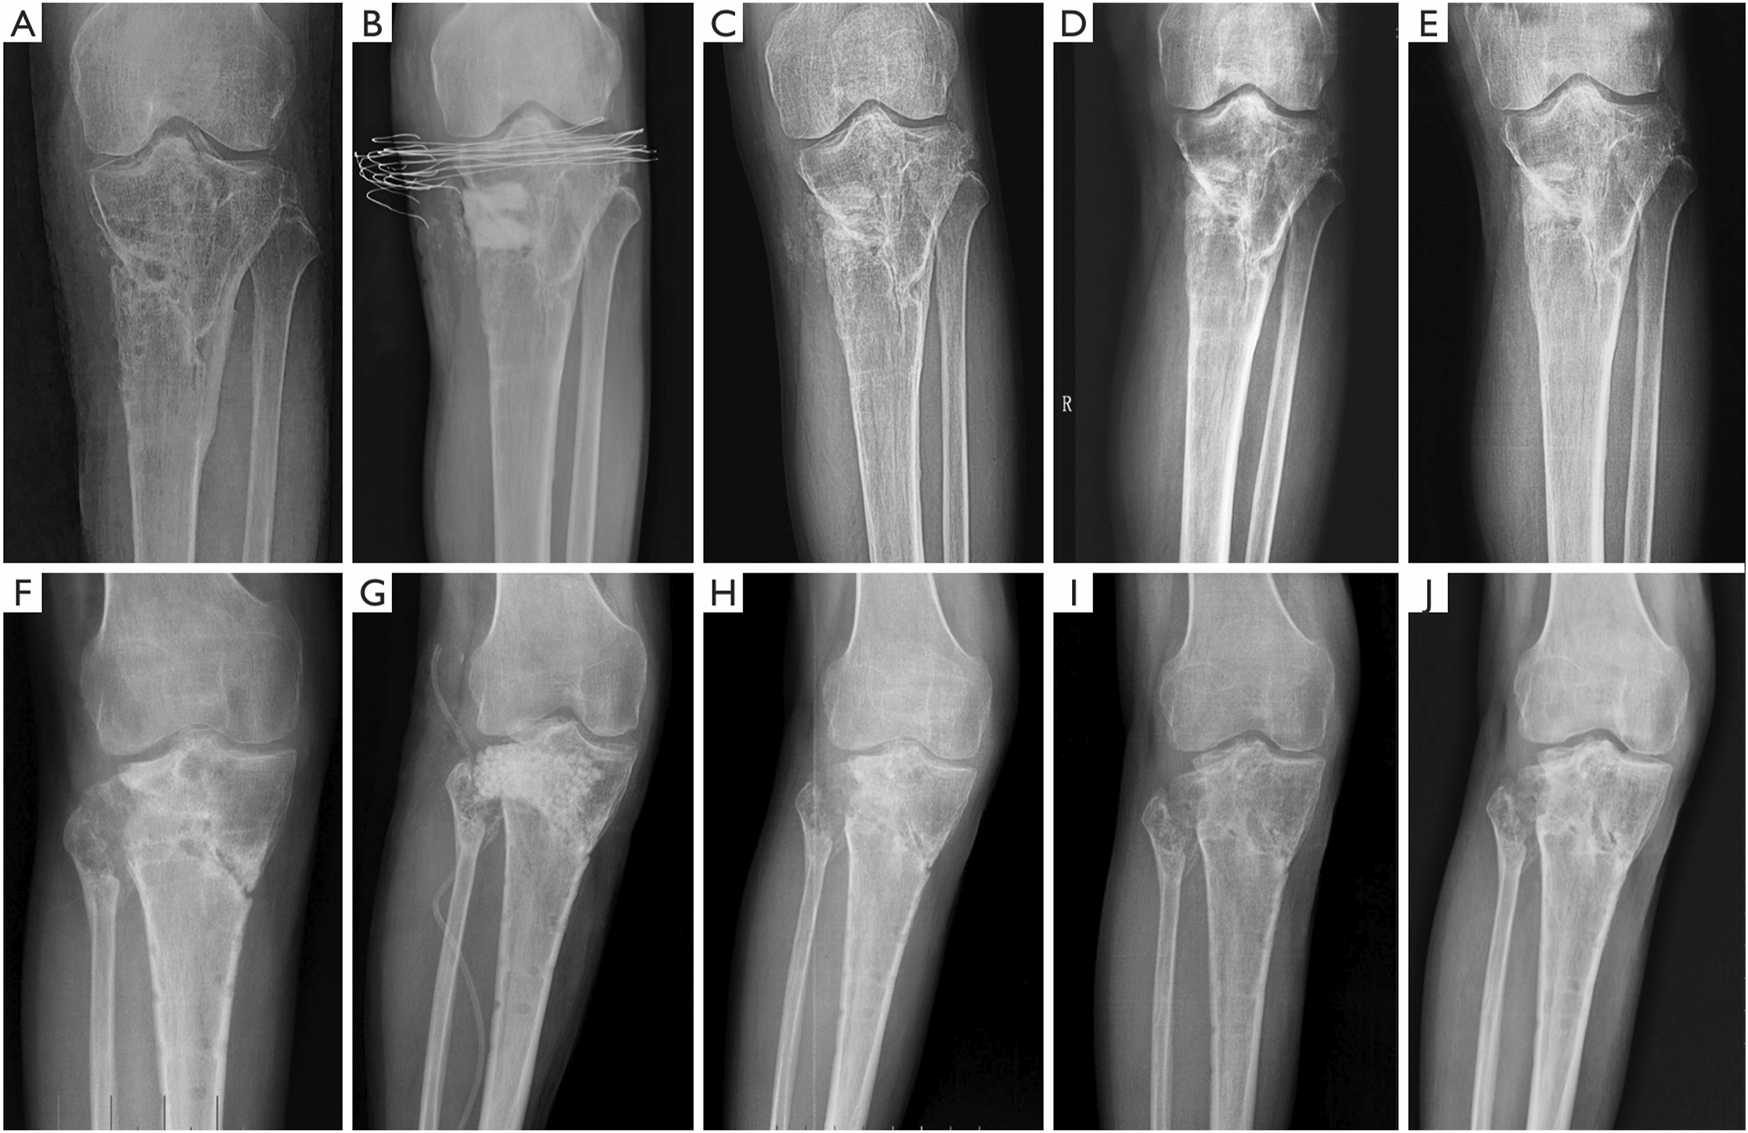

To harmonize the resorption rate of the bone cement matrix with the rate of new bone formation, a multifunctional calcium phosphate-calcium sulfate complex bone cement was developed, exhibiting antimicrobial, osseointegrative, and degradable properties. Building upon the established potential of this cement as an effective antibiotic delivery system, as demonstrated by Mistry et al. (2016) through animal experiments, Zhao et al. (2020) reported the first clinical application of calcium phosphate (dicalcium phosphate (DCP) + β-TCP)-calcium sulfate complex bone cement impregnated with vancomycin in the treatment of chronic osteomyelitis caused by S. aureus infection. When compared to vancomycin-impregnated CSC used as a control, the composite bone cement exhibited superior new bone growth and a lower rate of infection recurrence (Table 2; Figure 3).

FIGURE 3

Typical radiographs of chronic osteomyelitis treated with CS/CP preoperatively (A), immediately (B), at 3 months (C), at 6 months (D) and at 1 year (E) postoperatively. With the formation of new bone, the bone substitute composite was gradually absorbed and no new defects formed until the formation of new bone completed (E). Typical radiographs of chronic osteomyelitis treated with CS preoperatively (F), immediately (G), at 3 months (H), at 6 months (I) and at 1 year (J) postoperatively. Three months after the surgery, CS had been greatly absorbed. However, the new bone formation was slow and bone defect cavities still existed (H, I, J). CS, calcium sulfate; CP, calcium phosphate (Zhao et al., 2020). Reprinted with permission from. Copyright 2020 Annals of Palliative Medicine.